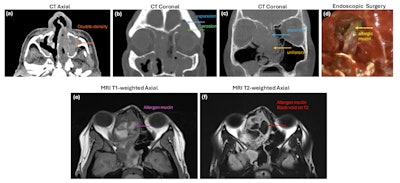

A workup for AFRS begins with a detailed patient history, including allergies and comorbidities such as asthma, along with a thorough physical examination and endoscopic evaluation. Additionally, understanding home and work exposures, particularly to mold, can be helpful. Allergy testing can reveal comorbid allergies including to fungus. Imaging is essential to assess the extent of the disease. CT imaging (Figure 1a-c) can delineate the extent of disease, expansion of the sinuses, and areas of bone erosion and deformity. Impacted sinuses are opacified with hypodense inflamed mucosa and central hyperattenuating areas of eosinophilic mucin (Figure 1d). Bony erosion and expansile disease into surrounding compartments can lead to compression of the orbit and brain. In more advanced cases, MRI is useful, with particular attention to T1 and T2 weighted images, which can show pathognomonic features of AFRS, such as central hypointensity on T1 and signal voids (Figure 1e-f) on T2 owing to the high protein concentration of allergic mucin. It is crucial to examine both T1 and T2 imaging sequences for an accurate understanding of the disease process.

Figure 1. Radiological features of AFRS from CT (1a-c), endoscopic surgery (1d) and MRI imaging (1e-f).Figure 1. Radiological features of AFRS from CT (1a-c), endoscopic surgery (1d) and MRI imaging (1e-f).